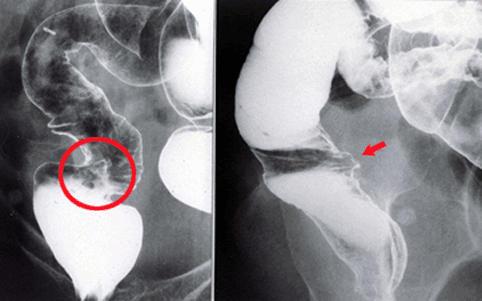

放射线性大肠炎

在直肠前壁可见有深溃疡的放射线性大肠炎病例 病例2

炎症性・溃疡性疾患/放射性大肠炎

部位(按器官分)

检查方法

40以上